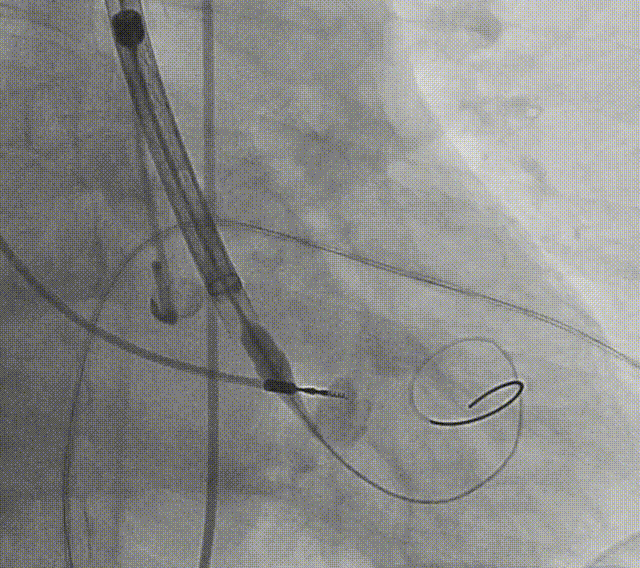

患者病史 术前超声提示:主动脉瓣退行性病变;中-重度狭窄并轻度返流;中-重度三尖瓣返流;中度肺高压 术前CT 三叶瓣,瓣叶增厚轻度钙化,右无交界有粘连,预计可以扩开,主动脉根部直径23.7mm,LVOT直径24.3mm,呈直筒型;双侧冠脉开口高度可,瓣叶长度小于冠脉开口上缘到主动脉根部的距离;窦部空间可,STJ、升主动脉内径可;主动脉水平夹角43.6°,非横位心;主动脉弓角、弓距可,左室内径可;外周入路无明显迂曲,有零星散状钙化,双侧股动脉内径可,均能通过20F大鞘,右股低分叉。 手术策略 推荐右侧股动脉为主入路使用20F大鞘,左侧股动脉为辅入路,右股分叉上方1cm穿刺;推荐使用22mm球囊预扩,预装AV26瓣膜,备AV29瓣膜,初始定位为真实瓣环上方3mm,瓣膜释放过程中释放张力使其自然下滑,工作位观察瓣膜稳定性,最终理想位置为零位;左右重合位:RAO23°CAU32°;右窦居中位:LAO5°CAU12°;左冠切线位:LAO34°CRA14°。 手术过程 术中右股动脉痉挛,内径变为3.8mm,遂更换左腋动脉入路;18球囊预扩,后植入AV26 ProStyle A®瓣膜;瓣膜精准释放于目标位置,超声显示无明显瓣周漏,血流动力学即刻改善。 术中右股动脉痉挛,内径变为3.8mm,更换左腋动脉 主动脉根部造影 18球囊预扩 初始定位 工作位观察 术后即刻表现:无瓣周漏,术后峰值压差10mmHg 术后3天复查超声峰值压差14mmHg Prostyle A®预装干瓣——助力临床最优化解决方案: 轻松过弓,精准可控:该病例经左腋动脉入路,输送系统较细的尺寸+柔顺的输送系统通过性能得到了很好的验证; 释放稳定:平衡的径向支撑力降低了释放过程中的张力,流入端小锥角设计能够迅速锚定贴边,80%可回收使得观察位和释放后的位置差距减少,大大提高了释放过程中的精准性,能够轻松应对高难度病例; 预装干瓣 便捷顺安:金仕生物专利抗钙化技术运用纳米技术去除组织内的细胞碎片和磷脂,封闭游离醛基,从根本上阻断了瓣膜钙化的多项因素,显著提升了瓣膜的耐久性;同时,相比较传统戊二醛保存方式,干式存储最大限度的保留心包的亲水亲油平衡,还原组织天然曲柔性,进一步保障了瓣叶开合,保证长期耐久性; 谢年谨教授 广东省人民医院 谢年谨教授指出:“对于外周血管条件较差的心脏瓣膜病患者,腋动脉路径凭借其更直接的解剖通路与更稳定的输送环境,为手术安全提供了重要保障,尤其适用于股动脉入路失败的复杂病例。该路径不仅能显著降低血管损伤、出血等并发症风险,还能通过更清晰的操作视野提升手术成功率;尤其在高龄、动脉硬化严重的患者群体中,腋动脉路径的适应性优势更为突出。 专家简介 荆志成 广东省人民医院 谢年谨 广东省人民医院 刘勇 广东省人民医院 · END ·